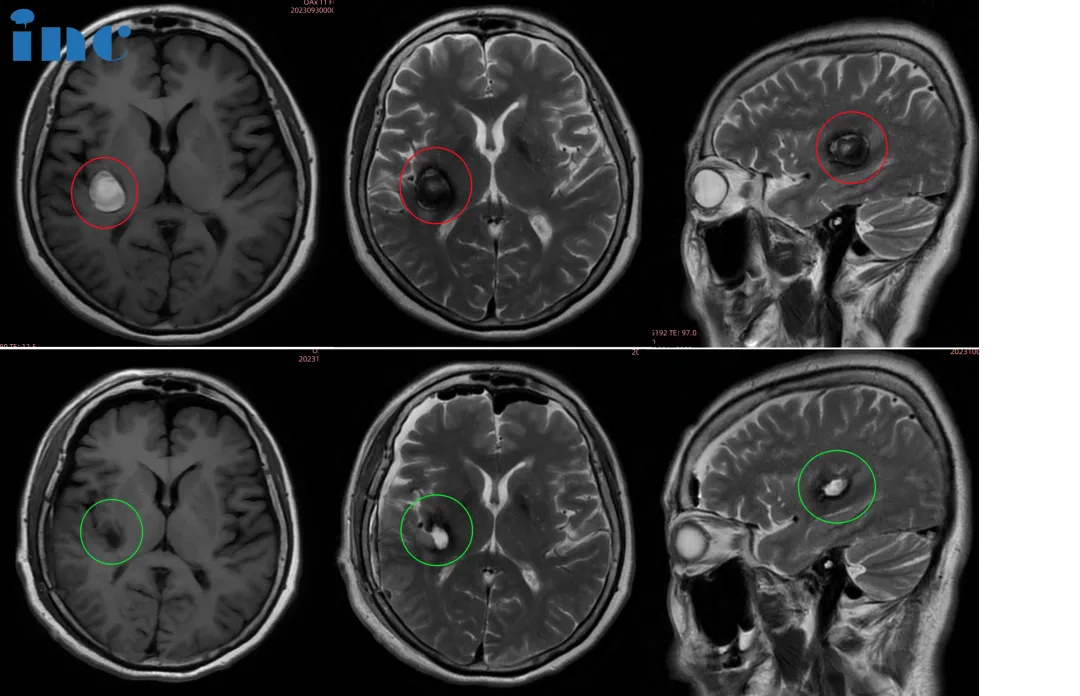

▼巴教授神经导航引导下切除基底神经节海绵状瘤。a,术前t1加权MR图像显示病变向内囊附近延伸。b,海绵状血管瘤瘤完全切除后的术后t2加权MRI

▼巴教授基底神经节海绵状血管瘤,54岁男性。该患者在神经导航的帮助下进行手术。A-C,术前MR图像显示右侧尾状核海绵状血管瘤。D,神经导航定位、皮肤切口等。E,海绵状血管瘤完全切除后的术后CT扫描。F,术后10天无神经功能缺损。